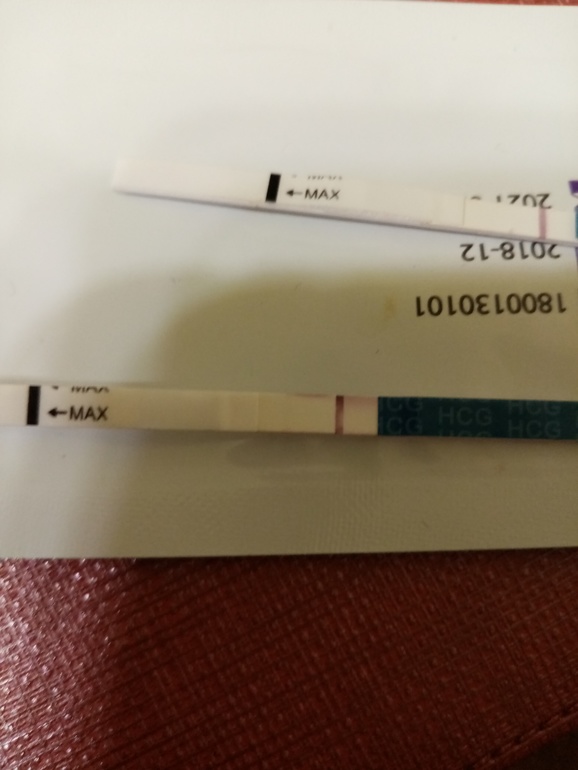

Гляделки. Есть полосочка? (Категория для тех, кто незнает свой ДПО)Сегодня 52 д. ц и 21 день задержки. 11 дней назад была на узи сказали киста(была в женской консультации) отправила результаты своему врачу, она прописала Норколут 10 дней. Вчера утром была последняя 💊. Сегодня ночью на работе очень болел живот. Пришла домой и сделала тест, это реагент? Как бы задержка уже большая и тест был бы уже гиперполосатый. Ну это я так вдрук на узи ошиблись😀

Норколут может 2 полоску дать, гормон всё-таки. На такой день задержки уже во всю полосатить должен тест

у меня в дневник фото тестов моих полосатый глянте

у меня в дневник фото тестов моих полосатый глянте